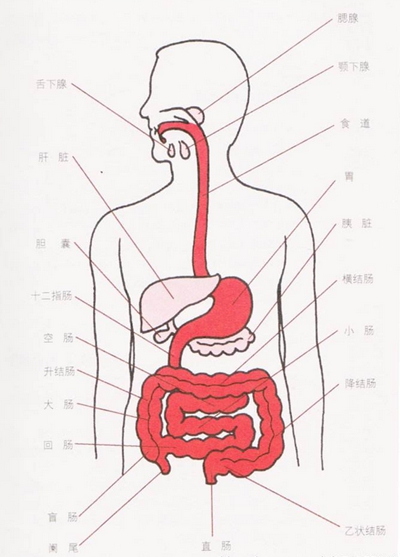

盲腸炎圖片

盲腸的位置 (50)

盲腸的位置 (6)

盲腸的位置 (7)

盲腸的位置 (8)

盲腸的位置 (9)

盲腸的位置 (46)

盲腸的位置 (47)

盲腸的位置 (48)

盲腸的位置 (49)

盲腸的位置 (5)

盲腸的位置 (42)

盲腸的位置 (43)

盲腸的位置 (44)

盲腸的位置 (45)

盲腸的位置 (41)

盲腸的位置 (40)

盲腸的位置 (30)

盲腸的位置 (31)

盲腸的位置 (32)

盲腸的位置 (33)